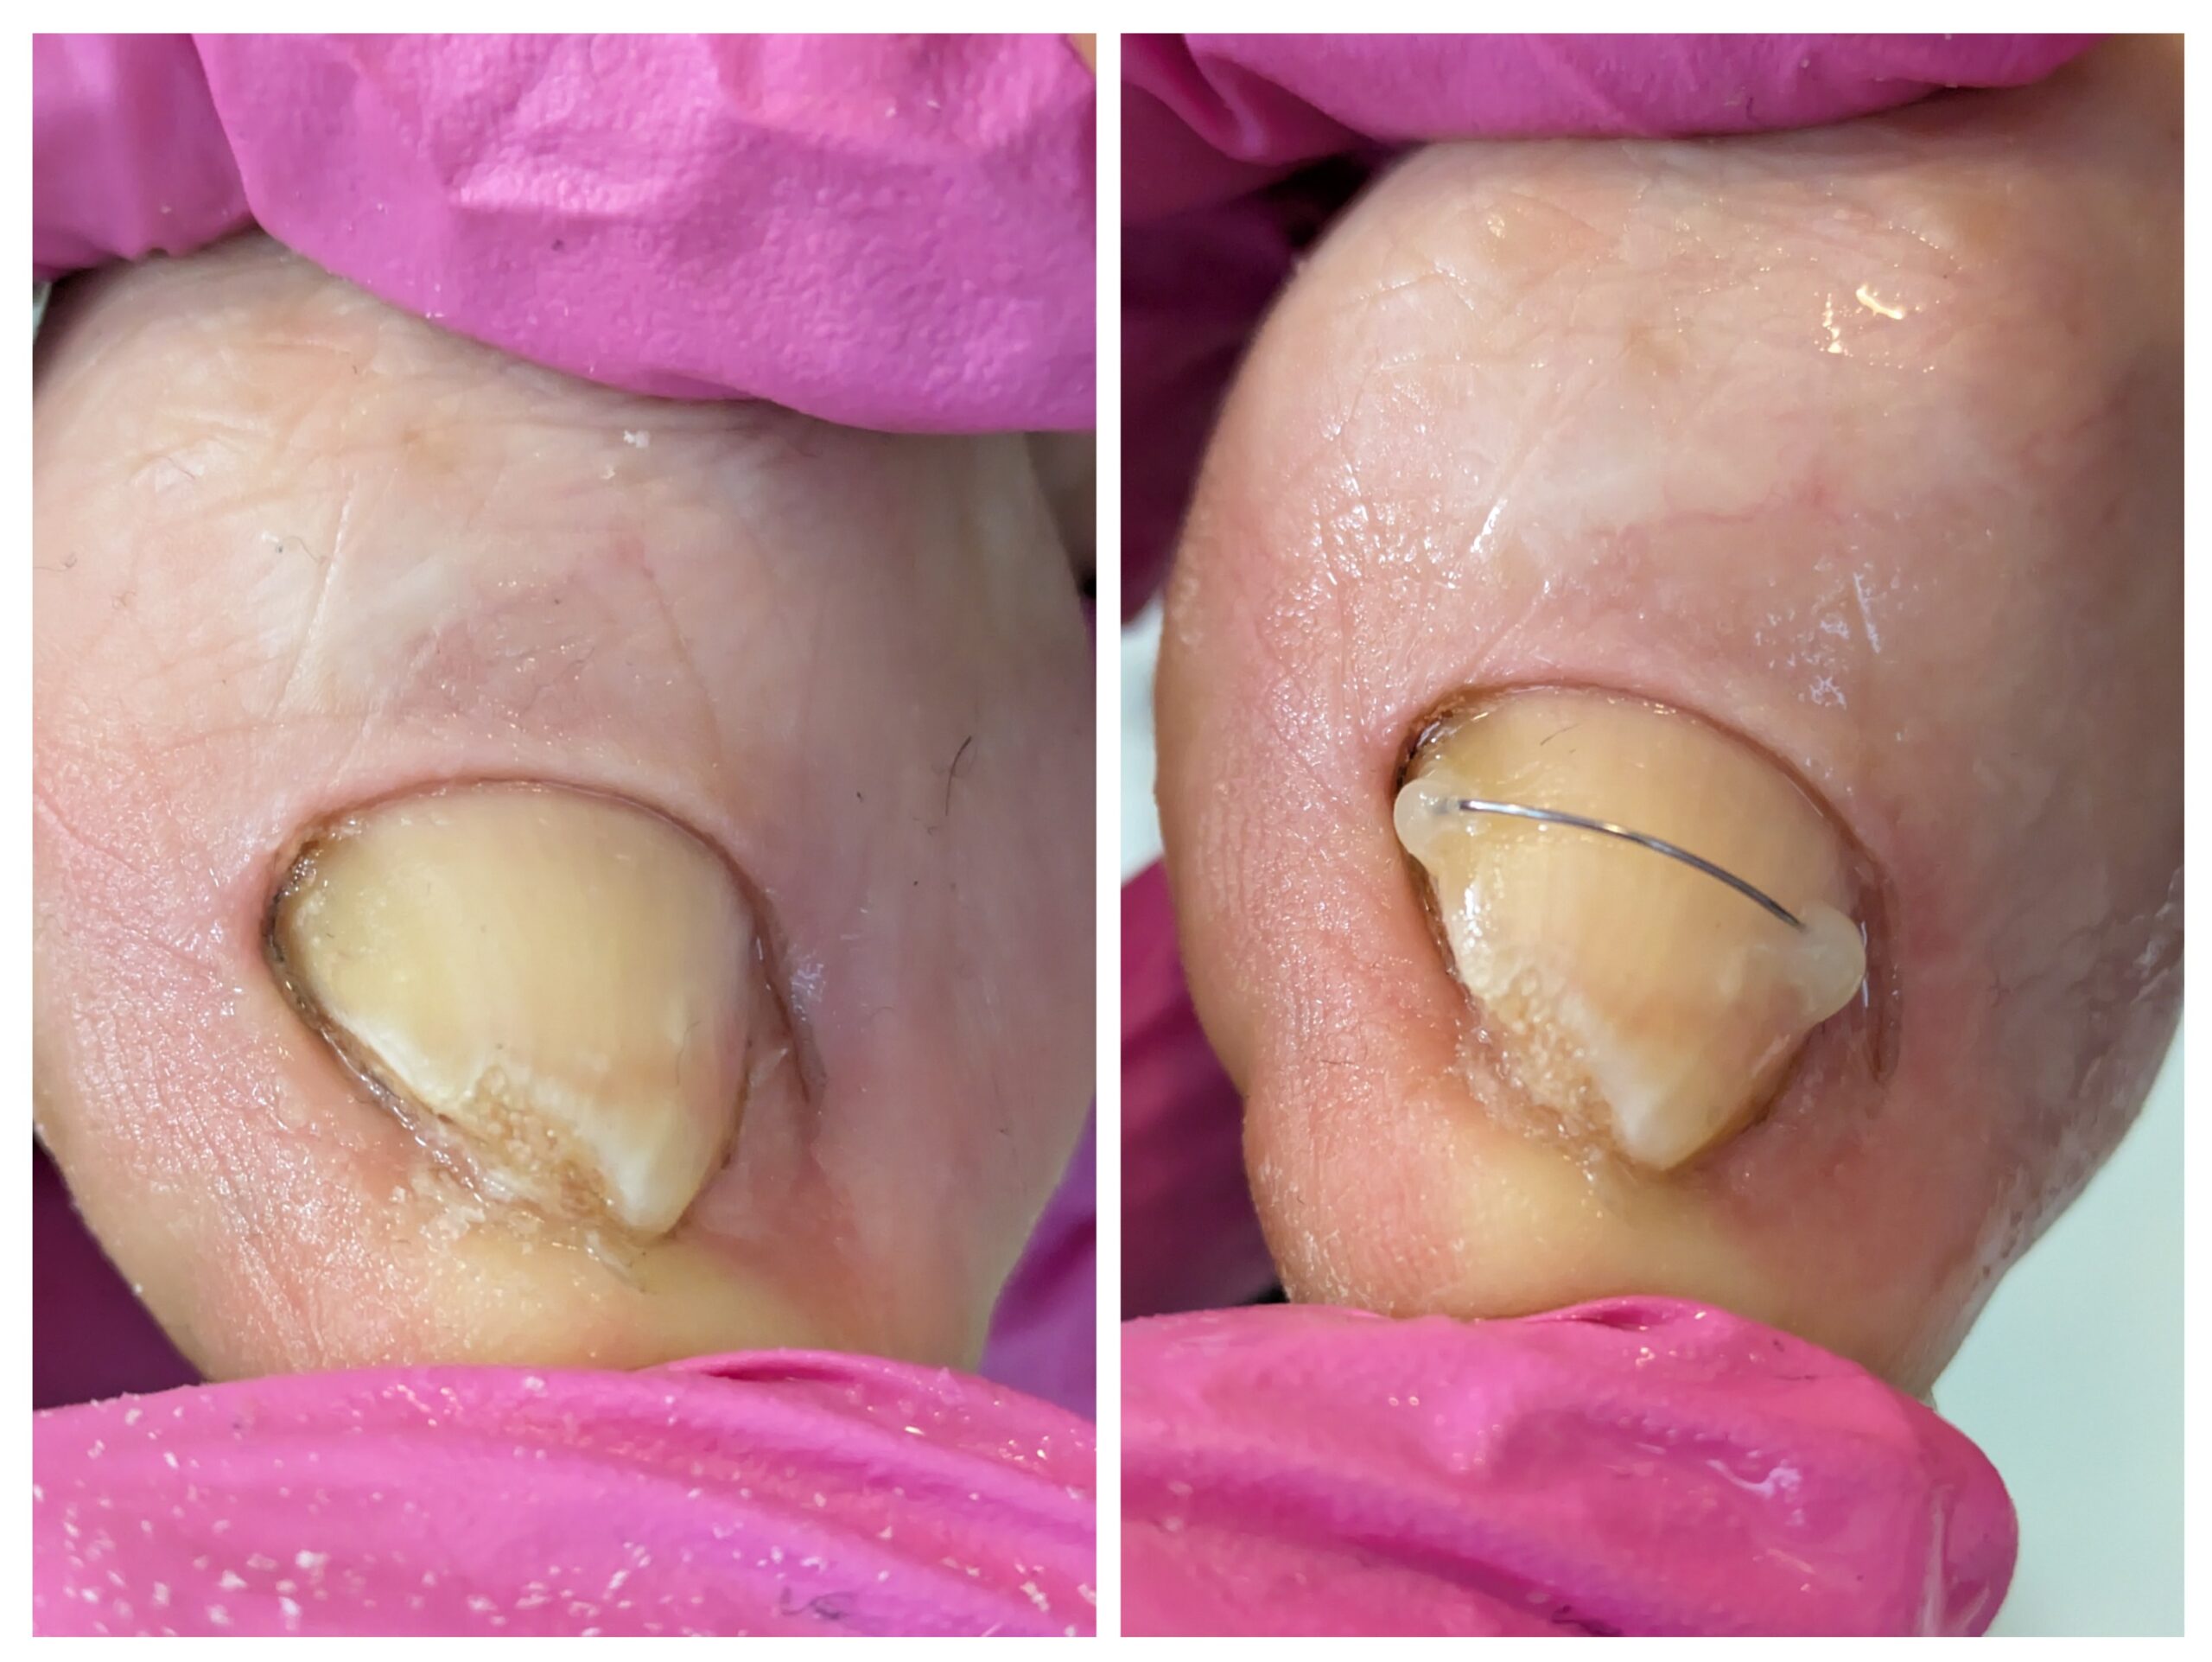

Terapia paznokci wrastających i wkręcających oraz ortonyksja

Paznokcie wrastające i wkręcające to częste i bolesne problemy w obrębie stóp, które mogą znacząco obniżać komfort codziennego funkcjonowania. Nieleczone, prowadzą do stanów zapalnych, infekcji, a nawet poważniejszych powikłań. W gabinecie podologicznym zapewniamy bezpieczną, skuteczną i indywidualnie dobraną terapię tych schorzeń.

Leczenie podologiczne

Podczas wizyty podolog przeprowadza dokładny wywiad oraz ocenę stanu paznokcia i tkanek okołopaznokciowych.

Terapia dobierana jest indywidualnie i może obejmować:

- bezbolesne opracowanie paznokcia

- odciążenie wałów paznokciowych

- zastosowanie specjalistycznych klamer ortonyksyjnych korygujących tor wzrostu paznokcia